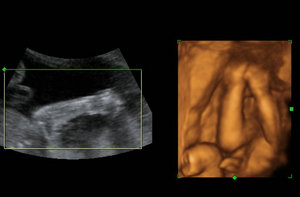

四维彩超需要价格?玛丽亚的专家对此表示到,我们知道,女性在怀孕期间里,是十分不易的,无论做什么都是小心翼翼的,就是想让肚中的小宝宝能够顺利的降生。而在孕期里,女性还要做好相关的孕期检查,通过这些检查可以确保胎儿在宫内的是否存在异常情况,如果问题可及时的发现。

做四维彩超,很多孕妇都会关心检查的费用问题。温馨提醒,由于地区的经济发展水平不同或是医院的收费情况不同,做四维彩超的费用也是不同的。一般来说四维彩超的费用在几百元左右,有的医院费用会略低或者是略高于这个数字,这与医院使用的仪器设备的收费情况不同等方面有关。

专家还指出,如果孕妇在检查的同时还做了其他的检查,那么检查的费用就会整体有所增加,孕妇要是做四维彩超,为了确保检查的准确性比较好的是到正规的医院进行检查。